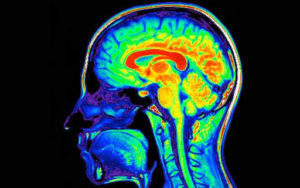

Igual que succeeix amb la cocaïna, passat l’efecte de plaer disminueixen els nivells de neurotransmissors fent que augmenti el desig de tornar a prendre amfetamines per contrarestar el malestar. Fins i tot mesos després d’haver suspès l’ús d’aquesta substància, els nivells de neurotransmissors com serotonina, dopamina i norepinefrina poden estar per sota dels nivells normals. És possible, a més, que, després d’un ús prolongat d’amfetamines, els nivells de neurotransmissors no tornin mai a ser normals.

L’ús a llarg termini d’amfetamines produeix una psicosi similar a l’esquizofrènia paranoide. En alguns casos, la psicosi pot produir-se també en utilitzar una dosi alta durant un curt període de temps.